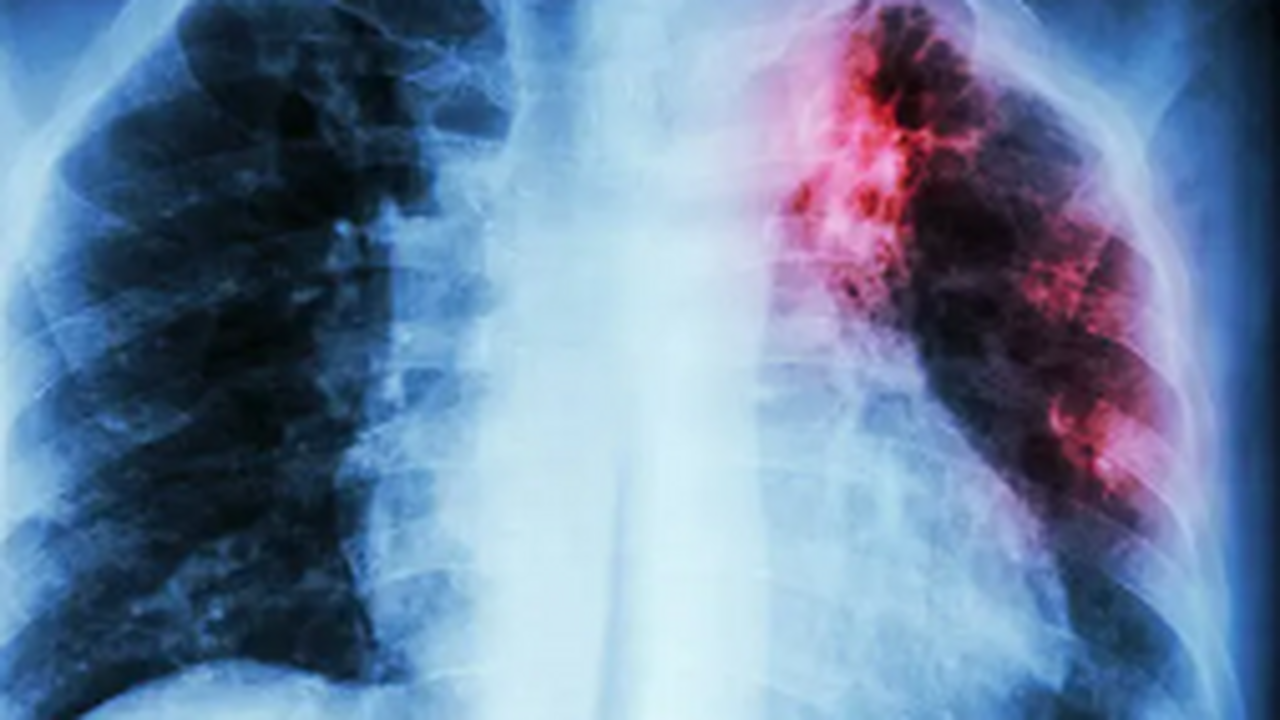

Это инфекционное заболевание часто развивается незаметно, а его возбудитель — палочка Коха — может долго сохраняться в окружающей среде. Чаще всего болезнь поражает лёгкие, но способна затрагивать и другие органы.